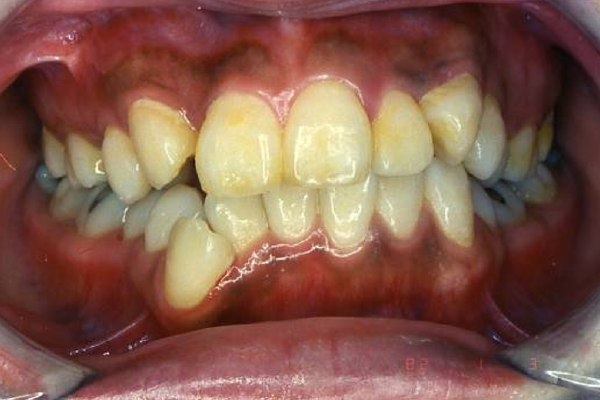

叢生の笑顔

①叢生(でこぼこ)の矯正治療例(30代女性・治療期間2年)

| 年齢・性別 | 30代女性 |

| 治療期間 | 2年 |

| 抜歯 | 上2本、下2本(小臼歯) |

| 治療費 | 50万円(調整費、保定費まで含む総額制) |

| 備考 | インビザライン |

| リスク・副作用 | 痛み・治療後の後戻り・歯根吸収・歯髄壊死・歯肉退縮 |